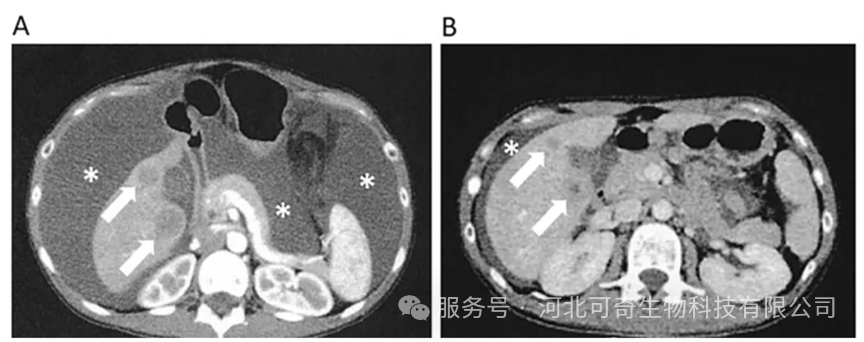

PET-CT显示治疗前后对照

(A)治疗前:原发性卵巢癌及肝、腹膜、肺等多处转移灶(黑色箭头)清晰可见。

(B)治疗 142 天后:原发性肿瘤明显缩小,肺转移灶与腹膜播散灶消失,肝转移灶显著缩小。白色箭头为腹股沟区接种 DC 疫苗后出现的炎症反应。

随着 NK 细胞治疗的推进,患者血液中性粒细胞 / 淋巴细胞比率(N/L)持续下降,逐渐转变为淋巴细胞占优势。第 142 天 PET-CT 显示,肺转移灶与腹膜播散灶完全消失,肝转移灶及原发病灶明显缩小。治疗期间,患者仅出现注射 DC 或 NK 细胞引发的发热,无其他明显副作用,为后续根治性手术创造了条件。